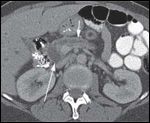

DR. PAUL RUSS: The initial CT scan of the abdomen with intravenous and oral contrast revealed a 2.7-cm, hypodense, hypovascular, solid mass in the head of the pancreas and also involving the uncinate process. In addition, there was dilatation of the pancreatic, intrahepatic and extrahepatic ducts without any evidence of distant metastatic or lymph node involvement. However, the second CT scan done, at the time of her clinic visit, showed post-surgical changes with an ill-defined soft tissue mass in the operative bed. There were also five new hypodense lesions in the liver, with the largest lesion in the anterior segment measuring 1.3 × 1.5 cm. There were two lesions in the dome, measuring 1.1 cm and 8 mm, along with two additional subcentimeter lesions in the right lobe (Figures 1A-1D, 2).

DR. PAUL RUSS: Because pancreatic adenocarcinoma is typically hypovascular compared to background pancreas and liver, the primary neoplasm is depicted as hypodense to the pancreas, and metastases as hypodense to the liver. However, some pancreatic adenocarcinomas remain occult, even with the use of advanced CT techniques, and in those cases the diagnosis can sometimes be surmised by using indirect, secondary signs like pancreatic and/or bile duct dilatation, and post-obstructive pancreatic atrophy. In this case, we see one of the typical hypodense lesions consistent with metastatic pancreatic cancer.